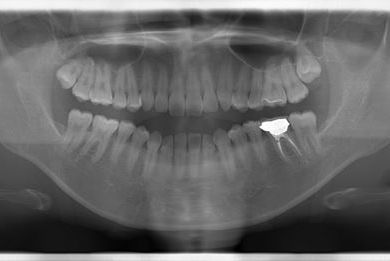

性別/年齢 女性 / 32歳

主訴 銀歯を白い歯にしたい。

治療方針 セラミック治療にて、審美的回復を行う。

治療内容 ハイブリッドセラミッククラウン1本、ハイブリッドセラミックインレー1本

治療部位

6

総治療費 89,250円

治療期間 4ヶ月